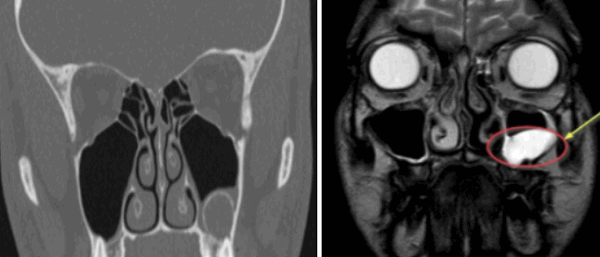

Слева — КТ-снимок одонтогенной кисты в верхнечелюстном синусе, справа — МР-фото образования (указано стрелкой) в гайморовой пазухе

Компьютерная и магнитно-резонансная томография отличаются по своей сути. КТ подразумевает воздействие на организм рентгеном. Изображение формируется в результате улавливания аппаратом Х-лучей, прошедших сквозь рассматриваемую анатомическую область. Плотные структуры организма в большей степени поглощают излучение, поэтому на снимках выглядят светлыми. КТ незаменима для исследования костей. Мягкие ткани лучше отображаются после введения контраста на основе йода. Компьютерная томография занимает несколько минут, поэтому востребована в экстренной медицине.